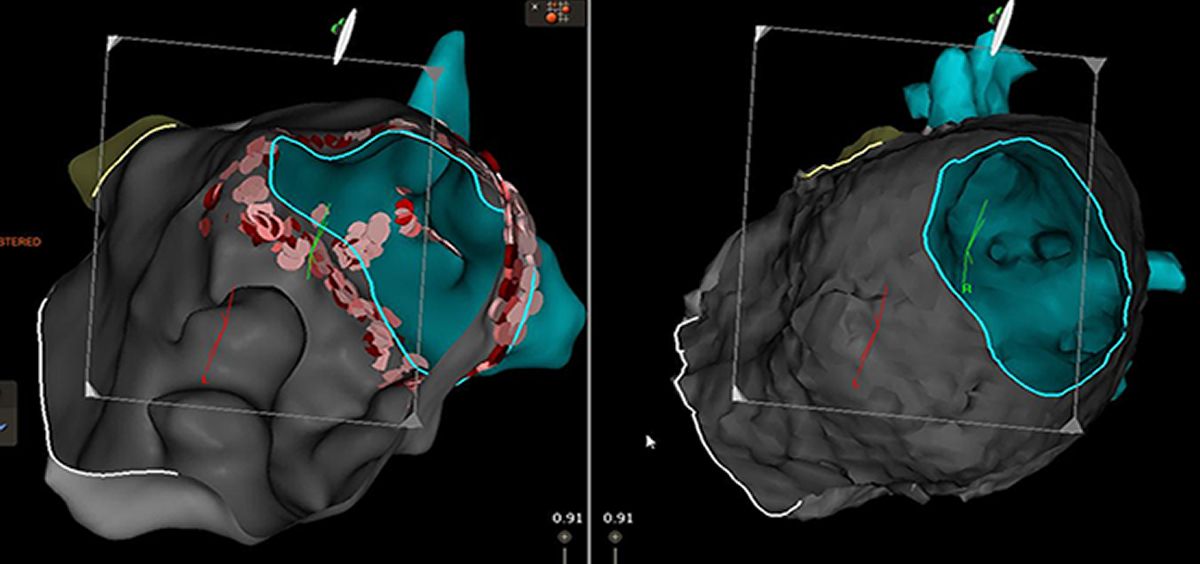

El sistema reconstruye un mapa electroanatómico en 3D de la cámara cardíaca codificada en color, con información electrofisiológica relevante y en tiempo real. El doctor Andreu Porta, cardiólogo especializado en arritmias miembro de la unidad, ha explicado que se trata de un sistema que utiliza una base similar a la del GPS de nuestro coche pero en 3 dimensiones. "Nos permite ver en cada momento con exactitud milimétrica en qué parte del corazón nos encontramos y qué actividad eléctrica existe", ha apuntado.